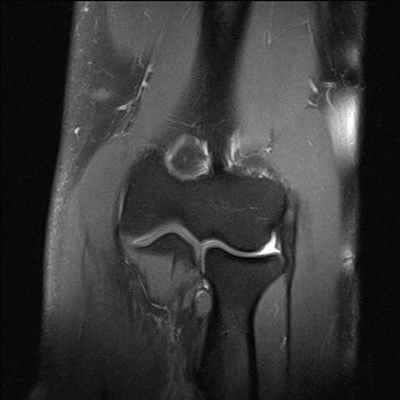

МРТ коленного сустава

Особая диагностическая ценность МРТ коленного сустава состоит в получении исчерпывающей картины дегенеративно-дистрофических изменений (хронические артриты и остеоартрозы, повреждения суставных поверхностей) и возможности визуализации самых мелких травм (разрывы связок, сухожилий, переломы), визуализация хряща с последующим его картированием для определения дистрофических и травматических изменений.

МРТ помогает с большой точностью установить полный или же частичный разрыв мениска, прекрасно и наглядно отображает состояние связок коленного сустава. При диагностировании передней крестообразной связки МРТ показывает разрывы ясно и четко в 96%. Магнитно-резонансная томография наглядно демонстрирует не только разрывы сухожилий, но и гораздо более тонкие проблемы, возникающие во внутренней структуре, сопряженные с воспалением или рубцеванием тканей, которые при неблагоприятном прогнозе могут вызвать определенные хронические заболевания.